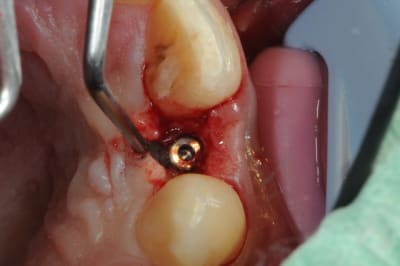

je reviens sur ce cas que j'ai un peu délaissé...

il est terminé, j'ai juste oublié de mettre la suite.

-cicatrisation

-mise en place vis de cica petit diamètre

-ensuite on augmente le diamètre en conservant et en gonflant les tissus gingivaux